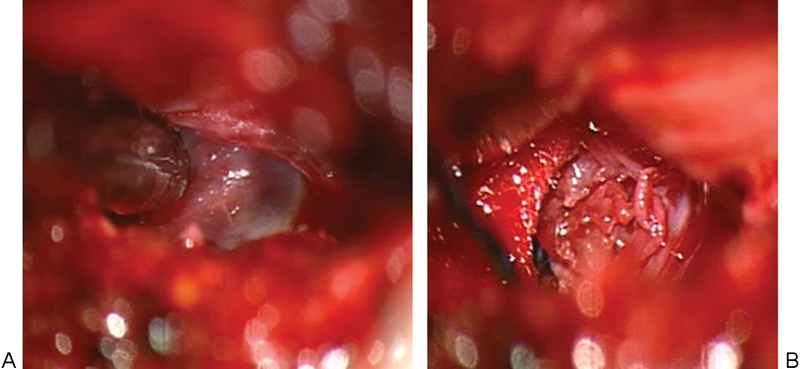

研究设计、个案报告及文献回顾。目的报告一例成功应用显微手术治疗腰椎间盘囊肿的病例,并对目前有关腰椎间盘囊肿诊断和治疗的文献进行综述。方法男性患者,43岁,表现为严重的背部疼痛,放射至右腿,并伴有右侧L3和L4皮节的感觉异常。腰椎磁共振成像显示在L3-L4椎间盘水平有椎管内、硬膜外占位性病变,导致神经结构受压。手术切除病变,诊断为腰椎间盘囊肿。术后症状改善,无并发症出院。对截至2014年2月发表的相关文章进行系统综述。检索关键文章以确定描述腰椎间盘囊肿的诊断和治疗方式以及显微手术与内窥镜治疗的有效性和安全性的研究。结论腰椎间盘囊肿是引起腰痛和神经根病的罕见原因。报告的病例很少;然而,关于它们的自然历史的结论性信息是不可获得的,最好的治疗方式仍然存在争议。我们认为腰椎间盘囊肿具有特殊的放射学和解剖学特征,应在腰痛和神经根病的罕见病因中进行鉴别诊断。

Study Design Case Report and review of the literature. Objective The objective of the article is to report an illustrative case successfully treated by microsurgery and to review the literature on the current evidence on diagnosis and management of lumbar discal cysts. Methods A 43-year-old male patient presented with severe back pain, radiating down to the right leg, as well as with paraesthesias in the right L3 and L4 dermatomes. Magnetic resonance imaging of the lumbar spine revealed an intraspinal, extradural space-occupying lesion at the L3-L4 disc level, causing compression of the neural structures. The lesion was surgically removed and a diagnosis of lumbar discal cyst was made. Postoperatively, symptoms improved and the patient was discharged with no complications. A systematic review of pertinent articles published up to February 2014 was performed. Key articles were searched to identify studies describing the diagnosis and management modalities of lumbar discal cysts and the comparative effectiveness and safety of microsurgery versus endoscopic treatment. Conclusions Discal cysts are rare causes of low back pain and radiculopathy. Few cases have been reported; however, conclusive information about their natural history is not available and the best mode of treatment remains controversial. We submit that lumbar intervertebral disc cysts, with their peculiar radiological and anatomic features, should be considered in the differential diagnosis among rare causes of low back pain and radiculopathy.